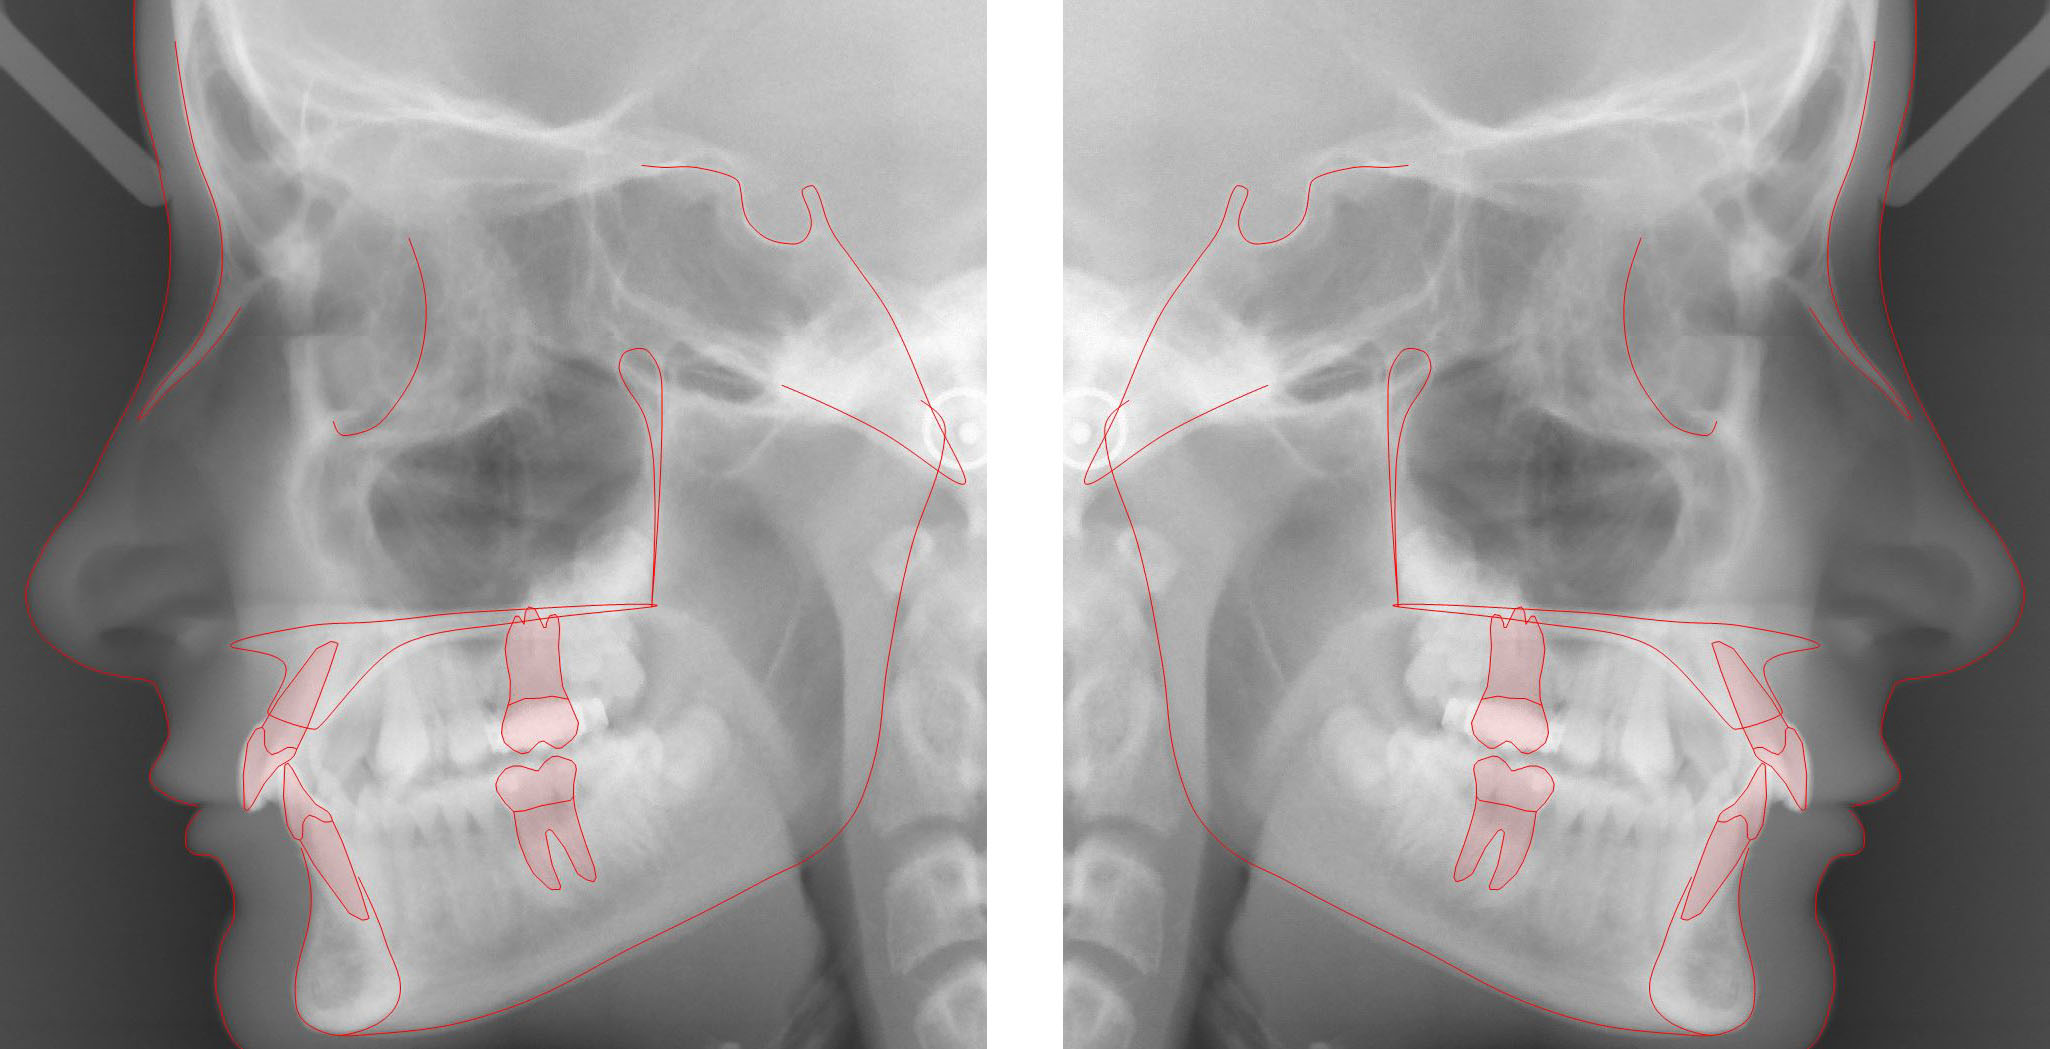

Tracing is the placement of graphic symbols on a digital tracing image, most likely a lateral x-ray image. Anatomic structures to be traced are hard and soft tissue landmarks (markers), teeth, hard tissue segments, a soft tissue profile line, and other structures.

Predefined graphic symbols for incisors are automatically drawn when the incisors’ markers are placed.

Symbols for canines, premolars, and molars are interactively placed directly on the x-ray image with two clicks of the mouse.

Hard tissue segments such as the maxilla and the mandible, and other anatomical structures are placed/drawn on the x-ray image using ready-made templates.

The soft tissue profile line is placed/drawn on the x-ray image using a predefined template and with the aid of automatic structure recognition.